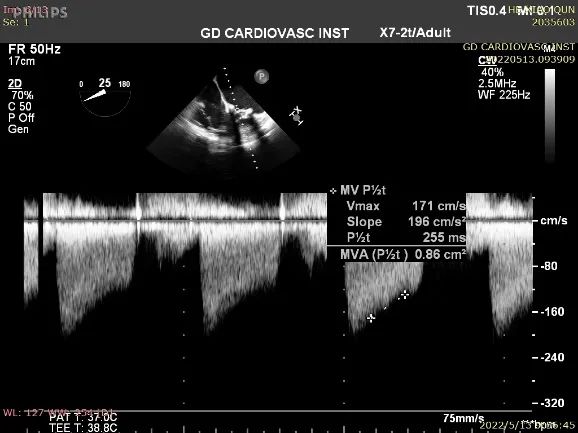

在手术当天行经食道心脏彩超检查,进一步评估患者心脏功能及瓣膜病变情况,测量二尖瓣原生物瓣内径为23.2mm,决定选择25mm J-Valve瓣膜。

2D和3D条件下测量衰败生物瓣瓣环内径

本例患者因是孕妇,为了尽可能减少X线的影响,术前未行CT检查,通过术中2D和3D TEE对衰败瓣环内径的精准测量,并结合术者的丰富经验,为患者选择了25mm J-Valve的瓣膜,成功完成手术,术后瓣膜形态、位置理想,血流动力学稳定。